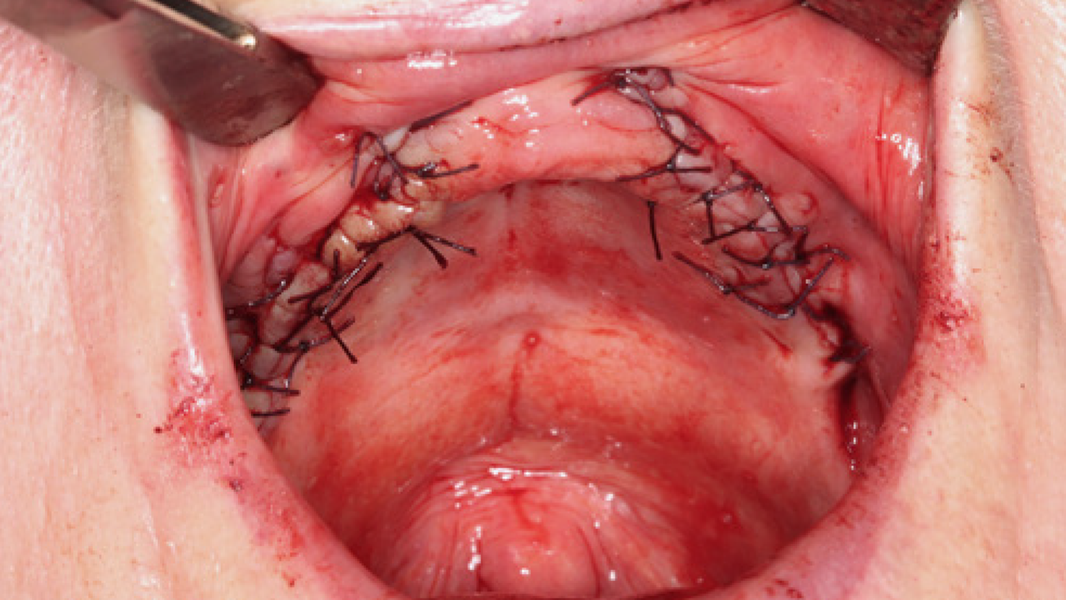

- Auf einer Skala von 1 bis 10 bewerteten die Kliniker die Heilung des Weichgewebes innerhalb der ersten zwei Wochen mit 8,8 bei den Erstanwendern.14, 17

15 Data on File. Limited Market Release. Clinical Case Documentation.